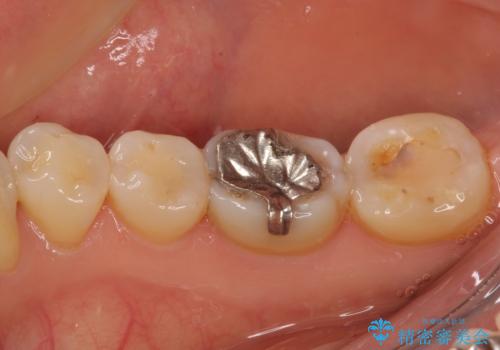

ゴールドは「白い歯」ではありませんが、銀歯の金属色とは異なり、非常にきれいな色合いが特徴です。

もちろん、適合が極めて良いという圧倒的メリットもゴールドクラウンやゴールドインレーの特徴です。